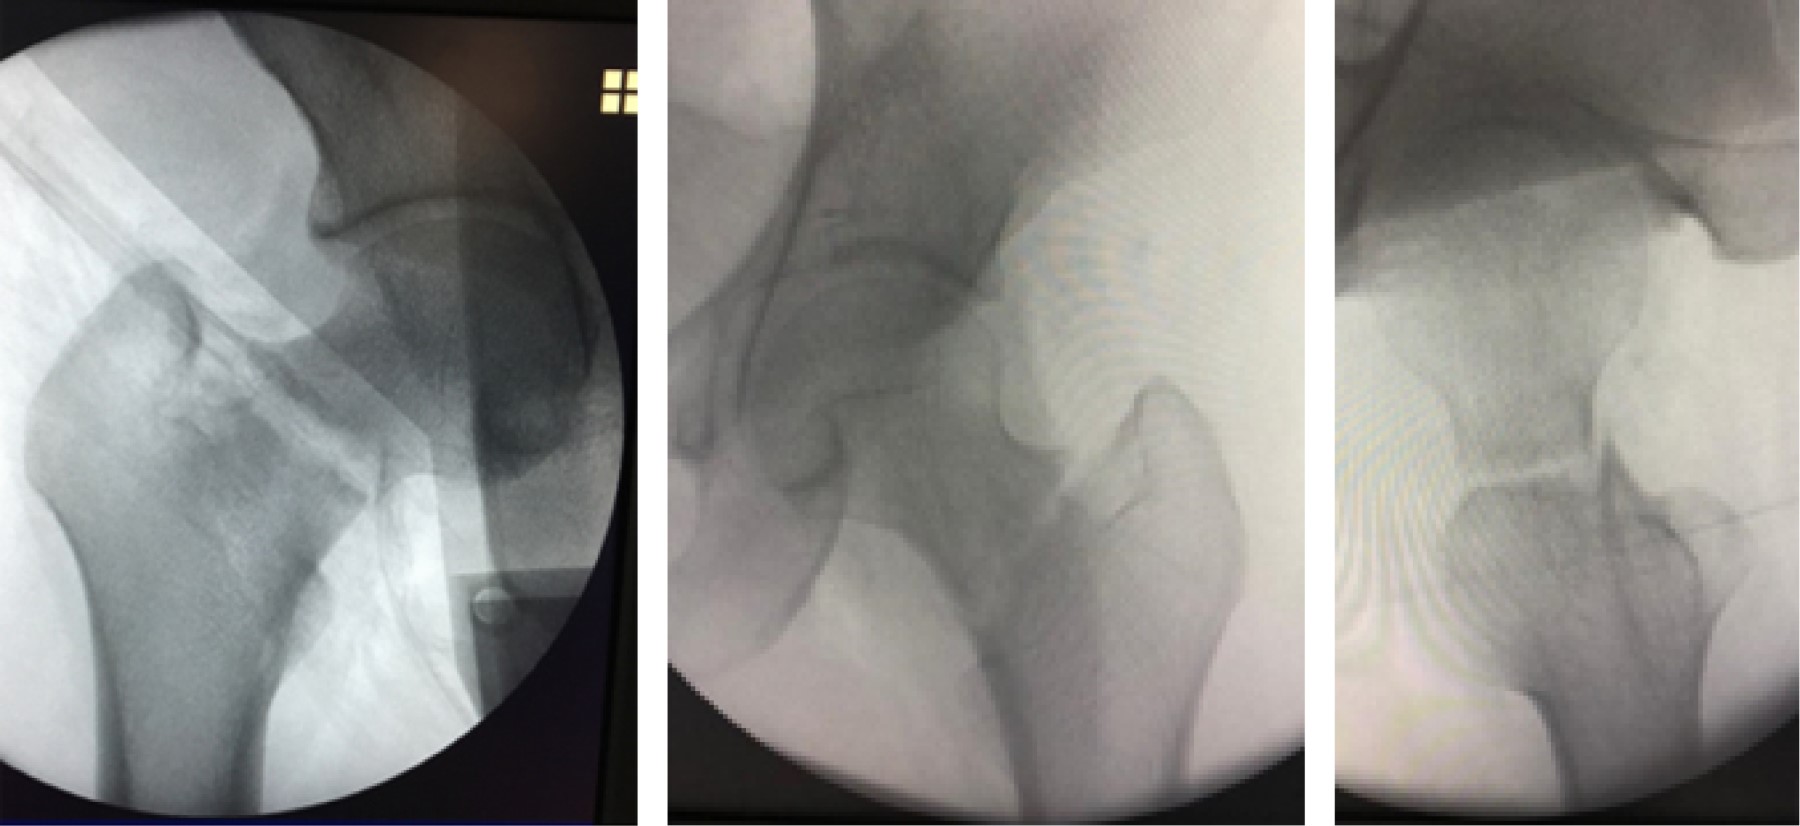

Stress hip fractures in men in military training

Introduction: Stress fractures are common injuries in the military population, they begin with the imposition of repetitive and excessive effort on the bone. This leads to the acceleration of bone remodeling and production of microfractures. The incidence, during their basic combat training, is 0.8 to 5.1% for men compared to 1.1 to 18% among women. We present a series of hip stress fractures in young male military men with progressive training of 8 hours a day over a period of 14 weeks. Results: Mean age 19.72 years, 4 transcervical and 7 basicervical fractures, 6 displaced and 5 no, 54.5 % right. All treated with osteosynthesis, DHHS (blockable compression plate system with hip spiral blade) in 3, cannulated screws in 3 and the proximal femoral fixation system with trochanteric nail (TFN) in five patients. The only common factor in all of them was intensive military training, pathology of metabolic or endocrine origin was ruled out. Onset of symptomatology measured in weeks with an average of 5. All patients had a delay in diagnosis with an average of 12.09 days at the time of definitive diagnosis. Conclusion: The diagnosis in stress fractures should be made based on clinical suspicion since the pain is insidious and in the report of the current condition patients fail to identify an exact moment as the onset of injury. The functional results were good and all of them managed to finish their military training.

Figure 1